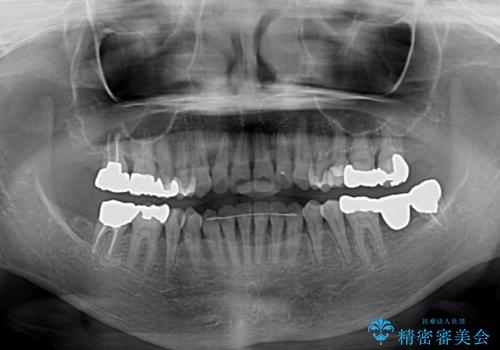

前歯の突出感と上下の隙間 インビザラインによる矯正治療

- 前歯の上下スペースと前歯の隙間を気にして来院された患者様です。

インビザラインにより上下の前歯の隙間を閉じながら、IPRを用いて口元の突出感を合わせて改善していくこととしました。

上下の隙間に舌が入り込むことが、すきっ歯やオープンバイトの原因であったため、舌の筋肉のトレーニングも並行して行い、後戻りの抑制を図りました。